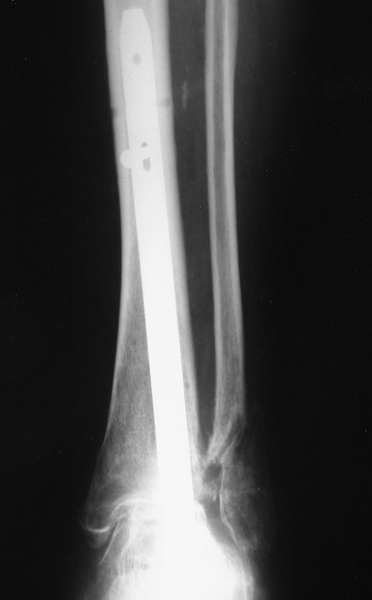

Можно: 65-летняя пациентка, оперирована по поводу несросшегося в гипсе перелома лодыжек с патологической вальгусной установкой стопы и выраженным нарушением опрной функции. Оперирована через 6 месяцев после травмы. Рентгенограммы через 4 месяца после операции.

С уважением, А.Семенистый.